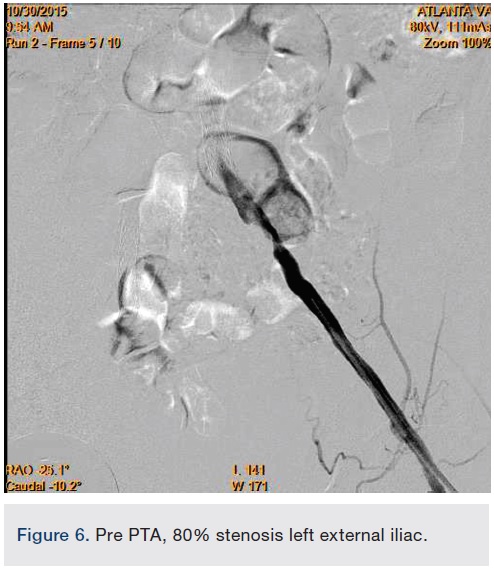

In view of the increased complexity of this situation and potentially prolonged procedure times with increased risk of complications, we chose to stage the procedure in two phases: peripheral and coronary. Accordingly, the patient was brought in, the left common femoral artery was accessed using a micropuncture technique, and a 10 cm, 7 French sheath was placed in the artery. Angiography of the left iliofemoral system was performed using a 4 French multipurpose catheter. This was followed by IVUS, revealing a 38.1 mm2 reference segment area and a minimum 8.6 mm2 stenosis area, equating to an 80% area stenosis within the left external iliac artery (Figures 5-6). The wire was exchanged for a 260 cm Rosen wire (Cook Medical) and the lesion was first predilated with a Workhorse II 6 mm balloon (AngioDynamics) at 10 atmospheres for 60 seconds for two successive inflations. The balloon was then removed over the wire and the short 7 French sheath was exchanged over the wire for a 25 cm, 7 French sheath, which was advanced over the Rosen wire into the distal aorta. An 8 mm x 38 mm x 120 mm iCast covered stent (Atrium Medical) was then advanced to the level of the stenosis and unsheathed via retraction of the 7 French long sheath. The stent was deployed at 10 atmospheres for 60 seconds. There was still a small waist in the proximal stent and this was post dilated with the stent balloon at 13 atmospheres for 90 seconds with excellent angiographic result and no evident perforation or dissection, yielding 0% residual stenosis (Figure 7).